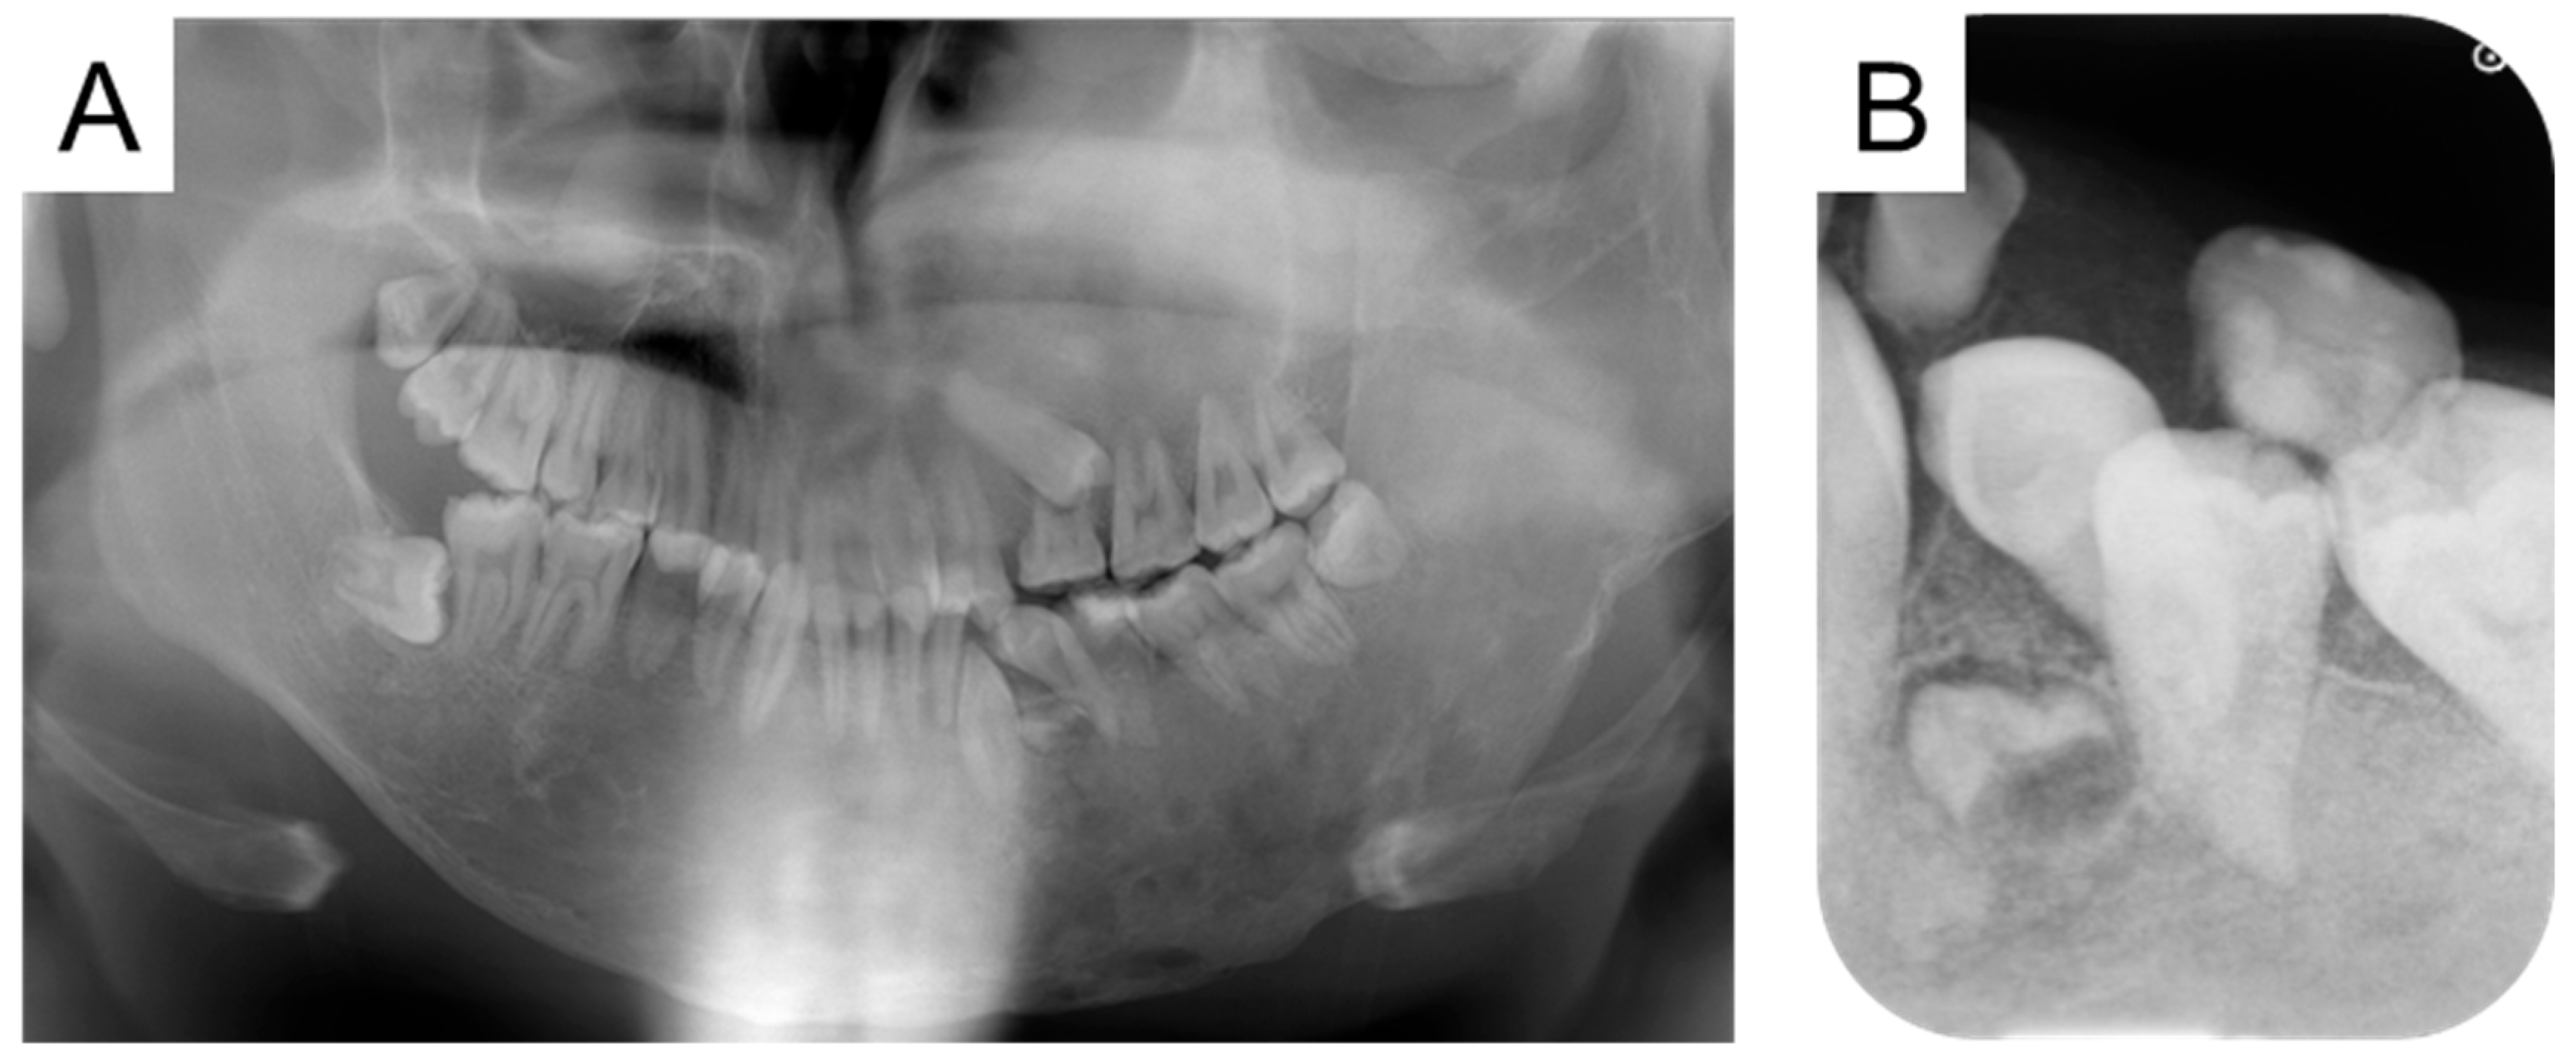

| 19 y 5 m | Discontinuation of bisphosphonate therapy |

| 19 y 9 m | Maxillary and mandibular osteotomies |

| 24 y 10 m | Left mandibular primary second molar extraction |